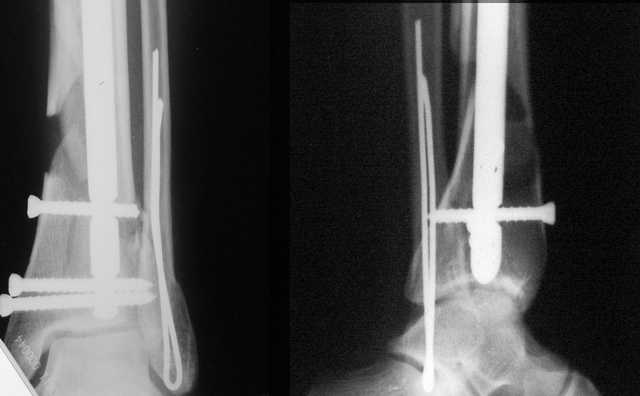

A propos fibular fixation if one is eager to stabilize it separately. In the fracture pattern a way of closed fixation by V-shaped stressed wire (advanced by colleagues from Moscow, prof. Lazarev A.F. et al.) must be excellent. We use indirect closed reduction by the external fixator. Example attached, that fibular fracture is even more suitable for plating but the wire did the job.

Еще, кстати, о фиксации лодыжки, если уж непременно хочется ее отдельно стабилизировать - при таком характере перелома замечательно должен сработать предложенный проф. Лазаревым с соратниками способ фиксации напряженной V-образной спицей. Опять же, открытая репозиция не нужна, мы делаем непрямую репозицию именно аппаратом. В приложении пример, там перелом малоберцовой куда менее поперечный, чем в данном случае, но все равно получилось закрыто без пластинки.

Второй случай сделан из одного разреза

Дж